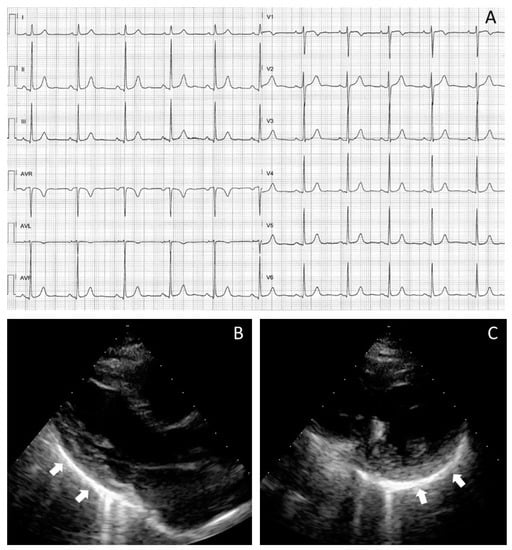

Finally, pericardial abnormalities were commonly observed after SARS-CoV2 pneumonia as pericardial thickening and/or hyper-echogenicity (19 patients; 66%), low-to-mild pericardial effusion (20 patients; 69%; 3 ± 3 mm on average), or both (24 patients; 83%). As exemplified in Figure 2, the pericardial involvement on TTE reflected the high prevalence of mild ST-T changes on ECG in most patients (23; 79%).

Figure 2. Cardiac manifestation in a patient fully recovered from COVID-19 pneumonia and with pericardial effusion developed during the acute phase of infection. The 12-lead electrocardiogram shows nonspecific repolarisation abnormalities on the inferior and right precordial leads (A). Different echocardiographic projections (parasternal long axis view in (B) and parasternal short axis view in (C)) display sequelae of a previous acute pericarditis (pericardial thickening and a dazzling hyper echogenicity with comet-like artefacts). Such TTE signs are more evident on the infero-lateral wall of the left atrium (arrows) with no sign of pericardial effusion.